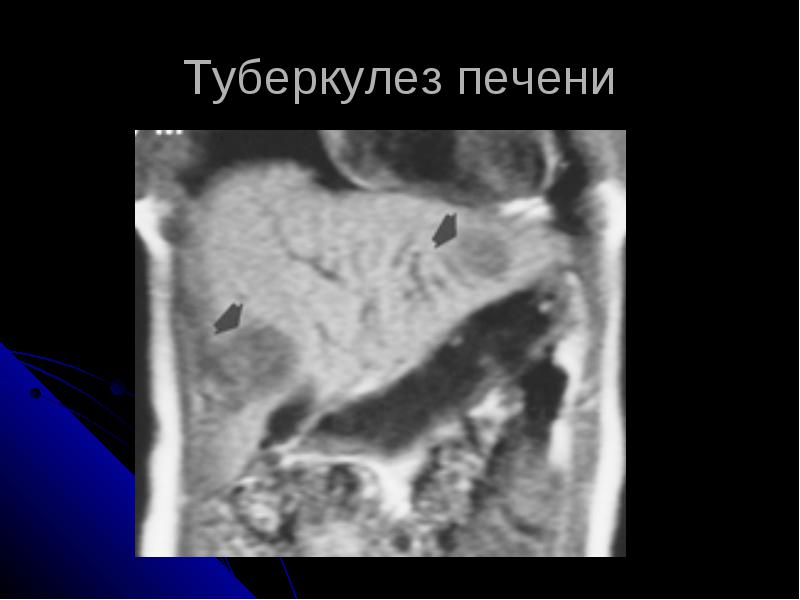

Туберкулез печени

Туберкулез печени сопровождает туберкулез кишечника в 79-99% случаев. Туберкулезные микобактерии проникают в печень гематогенным или лимфогеннным путем, возможно также распространение процесса по желчным ходам. Чаще всего наблюдаются милиарная форма или множественные туберкуломы печени с казеозным распадом в центре. Встречаются также неспецифические изменения в печени при туберкулезе легких в виде реактивного гепатита, жировой дистрофии, амилоидоза или лекарственного гепатита (при длительном применении туберкулостатических средств).

Диагноз туберкулеза печени подтверждается лапароскопией, пункционной биопсией печени, эхографией и сканированием.